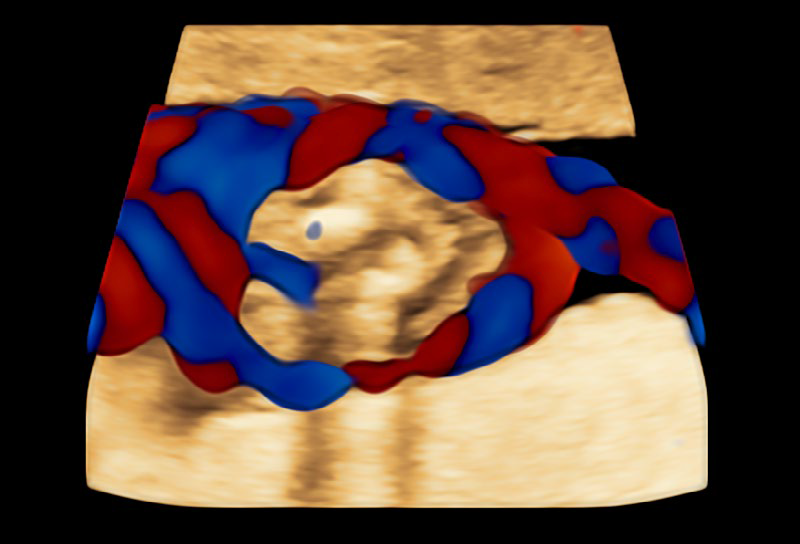

• RadiantflowTM

Separación mejorada entre vasos sanguíneos que proporciona la percepción de un flujo sanguíneo dinámico, añade información de altura y profundidad para una apariencia 3D, Menos destellos, límites vasculares mejorados e Identificación fácil y rápida incluso de los vasos más pequeños.